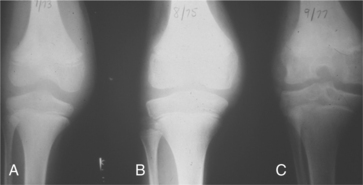

The mechanical trauma of normal weight-bearing motion may then impinge and further injure the inflamed synovium. Iron in the form of hemosiderin is deposited in the synovium, which impairs the production of synovial fluid. A vicious cycle is established as the synovium attempts to cleanse the joint of blood and debris, becoming more hypertrophic and susceptible to still further bleeding.11 Erosive damage of the cartilage follows these changes in the synovium with narrowing of the joint space (Fig. 14-12), erosions at the joint margins, and subchondral cyst formation. Collapse of the joint, joint sclerosis, and eventual spontaneous ankylosis may occur.

Figure 14-12 Stages of hemophilic arthropathy according to the Arnold-Hilgartner scale. A, Stage I (1973). B, Stage III (1975). C, Stage IV (1977). (Courtesy Mountain States Regional Hemophilia Center, Colorado State Treatment Program, Denver, 1995.)

In later stages of joint degeneration, chronic pain, severe loss of motion, muscle atrophy, crepitus, and joint deformities occur. Despite advances in medical management, target joints can progress to advanced arthropathy. This is most commonly seen in people with severe hemophilia. The articular cartilage softens, turns brown (due to hemosiderin), and becomes pitted and fragmented. The inflamed synovium is thick and highly vascularized and can grow over the joint surfaces, becoming pannus.

Eventually, lesions in the deeper layers of cartilage result in subchondral bone breakdown and the formation of subchondral cysts. Osteophyte formation occurs along the edges of the joint (Box 14-7 and Table 14-6). With the destruction of the cartilage, little to no joint space is left. This bone-on-bone contact can lead to significant pain, limitation of motion, joint malalignment, muscle atrophy, functional impairment, and disability.

Classification of Hemophilic Arthropathy.: Several different classification scales are used to identify progression of hemophilic arthropathy. The Arnold-Hilgartner and Pettersson score classification scales have been in use for many years. With the Arnold-Hilgartner scale, the arthropathy is divided into stages that are assumed to be progres- sive. With the Pettersson score, a number of specific findings are evaluated and the additive sum of the assigned points is calculated.